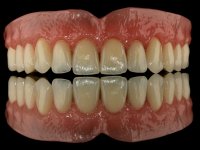

The overdentures with a metallic framework were fabricated over the bars, according to the silicone walls previously made. Before finishing the dentures, a new functional and aesthetic evaluation of the teeth was done, together with a new jet-bite registration to allow small occlusal adjustments.

The bars were finally screwed over the implants with the adequate torque and the overdentures set-in-place. Maintenance instructions were given to the patient regarding oral hygiene and overdentures insertion / removal.